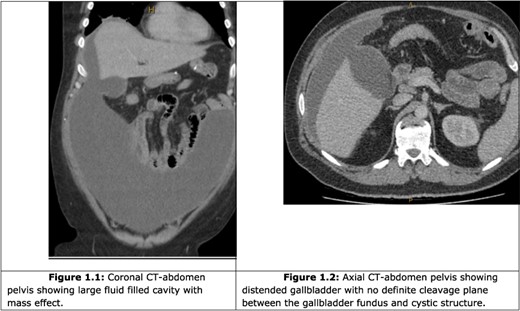

A computer tomography (CT) abdomen and pelvis with contrast was ordered (Fig. 1), which demonstrated a fluid-filled abdominal collection continuous with a distended gallbladder. The patient was referred to a local general surgeon, and underwent a positron emission tomography (PET) study to rule out intra-abdominal malignancy (Fig. 2). The differentials included primary mucinous tumour of the gallbladder, duplication cyst and pseudomyxoma peritonei.